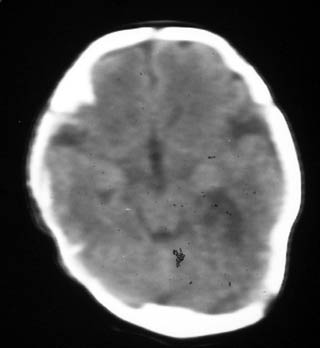

透明隔缺如

透明隔缺如。

这是一个早产儿(大约34周左右)的片子,可以是透明隔缺如,但往往是错误的。

视-隔发育不良:视-隔发育不良是罕见的中线结构前部畸形,主要特征为透明隔缺如,一般常见于垂体性侏儒症。ct表现为正常的透明隔缺如,双侧侧脑室前角及体部融合为一单脑室,侧脑室及第三脑室中度扩大,侧脑室前角在轴位像上呈反三角形,胼胝体压部变薄。约半数患者还伴有其它脑裂畸形改变。

胼胝体发育不全:胼胝体发育不全病因未完全确定,与遗传因素、母体感染或血管因素有关。胼胝体发育不全还可合并半球间裂囊肿、脂肪瘤、透明隔发育不全等。ct表现:半球间裂过深,第三脑室向前上移位,两侧侧脑室扩大,体部分离,呈反“八”字型或平行状。可伴随脑裂畸形、巨脑回、半脑间裂、蛛网膜囊肿及透明隔缺如等

透明隔缺如,支持。